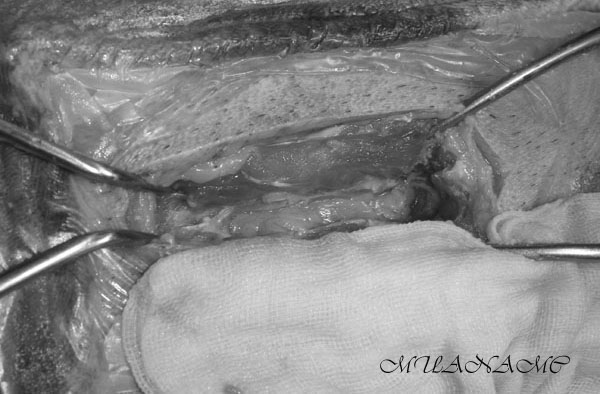

第二腰椎旁的肌肉層出現嚴重瘀血,與脊髓造影的定位符合。

(因畫面血腥故以黑白處理)